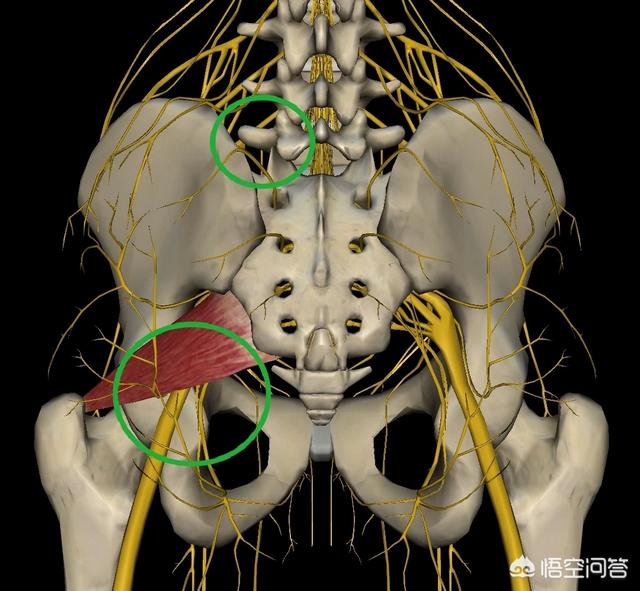

有时候,腰椎间盘突出症的人腰腿疼加重,不是腰椎间盘突出造成的,是由于长期的腰腿痛,造成臀肌劳损,劳损造成神经卡压,进一步加重症状表现!

最多见的例如,L4-5椎间盘突出症,造成臀部外侧和腿外侧疼痛麻木,可以诱发臀中肌综合征,进一步加重臀部和腿外侧痛!

L5-s1椎间盘突出症,造成臀部后侧疼痛,造成梨状肌紧张,压迫刺激坐骨神经,诱发臀部和腿后侧疼痛,和椎间盘突出症混合!